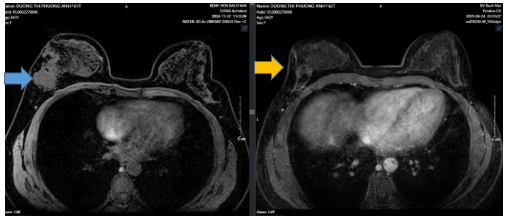

Hình 3:

Trước điều trị khối u vú phải ~70x59x37mm (mũi tên xanh), xâm lấn da ~34mm. Hạch thuộc chặng 1lớn nhất ~9x14mm, hạch chặng 2 ~5mm. Sau điều trị u vú phải ~16x23x36mm (sau điều trị mũi tên vàng), tổn thương xâm lấn da ~ 25mmHố nách bên phải chặng I có vài hach, còn rốn hạch vỏ hạch dày, lớn nhất ~ 4x6mm.